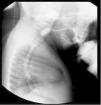

Presentamos un paciente masculino conocido por gastropediatría desde los 7meses de vida, con historia desde el primer día de síntomas respiratorios altos, reflujo nasofaríngeo predominantemente nocturno, adicionalmente con episodios broncoobstructivos recurrentes y episodios de apnea, tos durante la lactancia, sialorrea y mal manejo de secreciones. Con la alimentación complementaria presentó atragantamiento, salida de contenido alimentario por nariz, vómito y regurgitación ocasional. En la primera consulta las medidas antropométricas eran: peso: 7.65kg (–0.87DE); talla: 70cm (0.08DE); P/T (–1.18DE). Examen físico sin alteraciones. Por clínica de disfagia orofaríngea se realizó serie esofagogastroduodenal (SEGD), en la cual se documentó disminución del 60% de la luz esofágica cervical entre C3 y C4 (fig. 1), sugiriendo un espasmo del cricofaríngeo vs anillo vascular. En la esofagogastroduodenoscopia (EGD) se observó disminución del 60% de la luz del cricofaríngeo, que impedía franquearlo. Se realizó a los 8meses de vida la primera sesión de dilatación endoscópica, con mejoría de la disfagia y de los síntomas respiratorios. Se sospechó acalasia cricofaríngea. La manometría esofágica de alta resolución con sonda en estado sólido de 4.2mm de diámetro externo y 36 sensores mostró un patrón de presurización anormal en el cricofaríngeo compatible con AC (fig. 2). El paciente estuvo libre de síntomas hasta los 28 meses de vida. Posteriormente presentó recurrencia de la disfagia. Hasta el momento el paciente ha requerido dos dilataciones endoscópicas, a los 30 y a los 46meses, respectivamente, utilizando en la primera dilatación un balón de 8mm avanzando progresivamente con 10mm, 12mm, hasta 15mm. Actualmente tiene 56 meses de vida, sin disfagia, ni nuevos eventos broncoobstructivos, con adecuada ganancia ponderal.

El estudio de abordaje inicial es la SEGD o la cinevideodeglución, que evalúan el paso de contraste o de alimentos a través de la faringe, y signos de penetración y/o aspiración a la vía aérea5. Se mencionan hallazgos típicos, como el paso filiforme por el esófago cervical, la acumulación en la faringe, la regurgitación nasal o la aspiración del contraste, y la protrusión posterior en la unión faringoesofágica a nivel de C5-C66. La manometría esofágica es el método diagnóstico confirmatorio, ya que evalúa las presiones de apertura del esfínter esofágico superior (EES)4,6. En la AC se ha descrito elevación de las presiones en reposo del EES y ausencia de la relajación de este durante la deglución, con panpresurización, hallazgos encontrados en nuestro paciente (fig. 2). Algunos autores sugieren la EGD como parte del estudio de rutina para la AC, siendo característico el espasmo en el introito esofágico6. Nuestro paciente presentó todas las alteraciones que se refieren en la literatura en todos los estudios mencionados anteriormente.